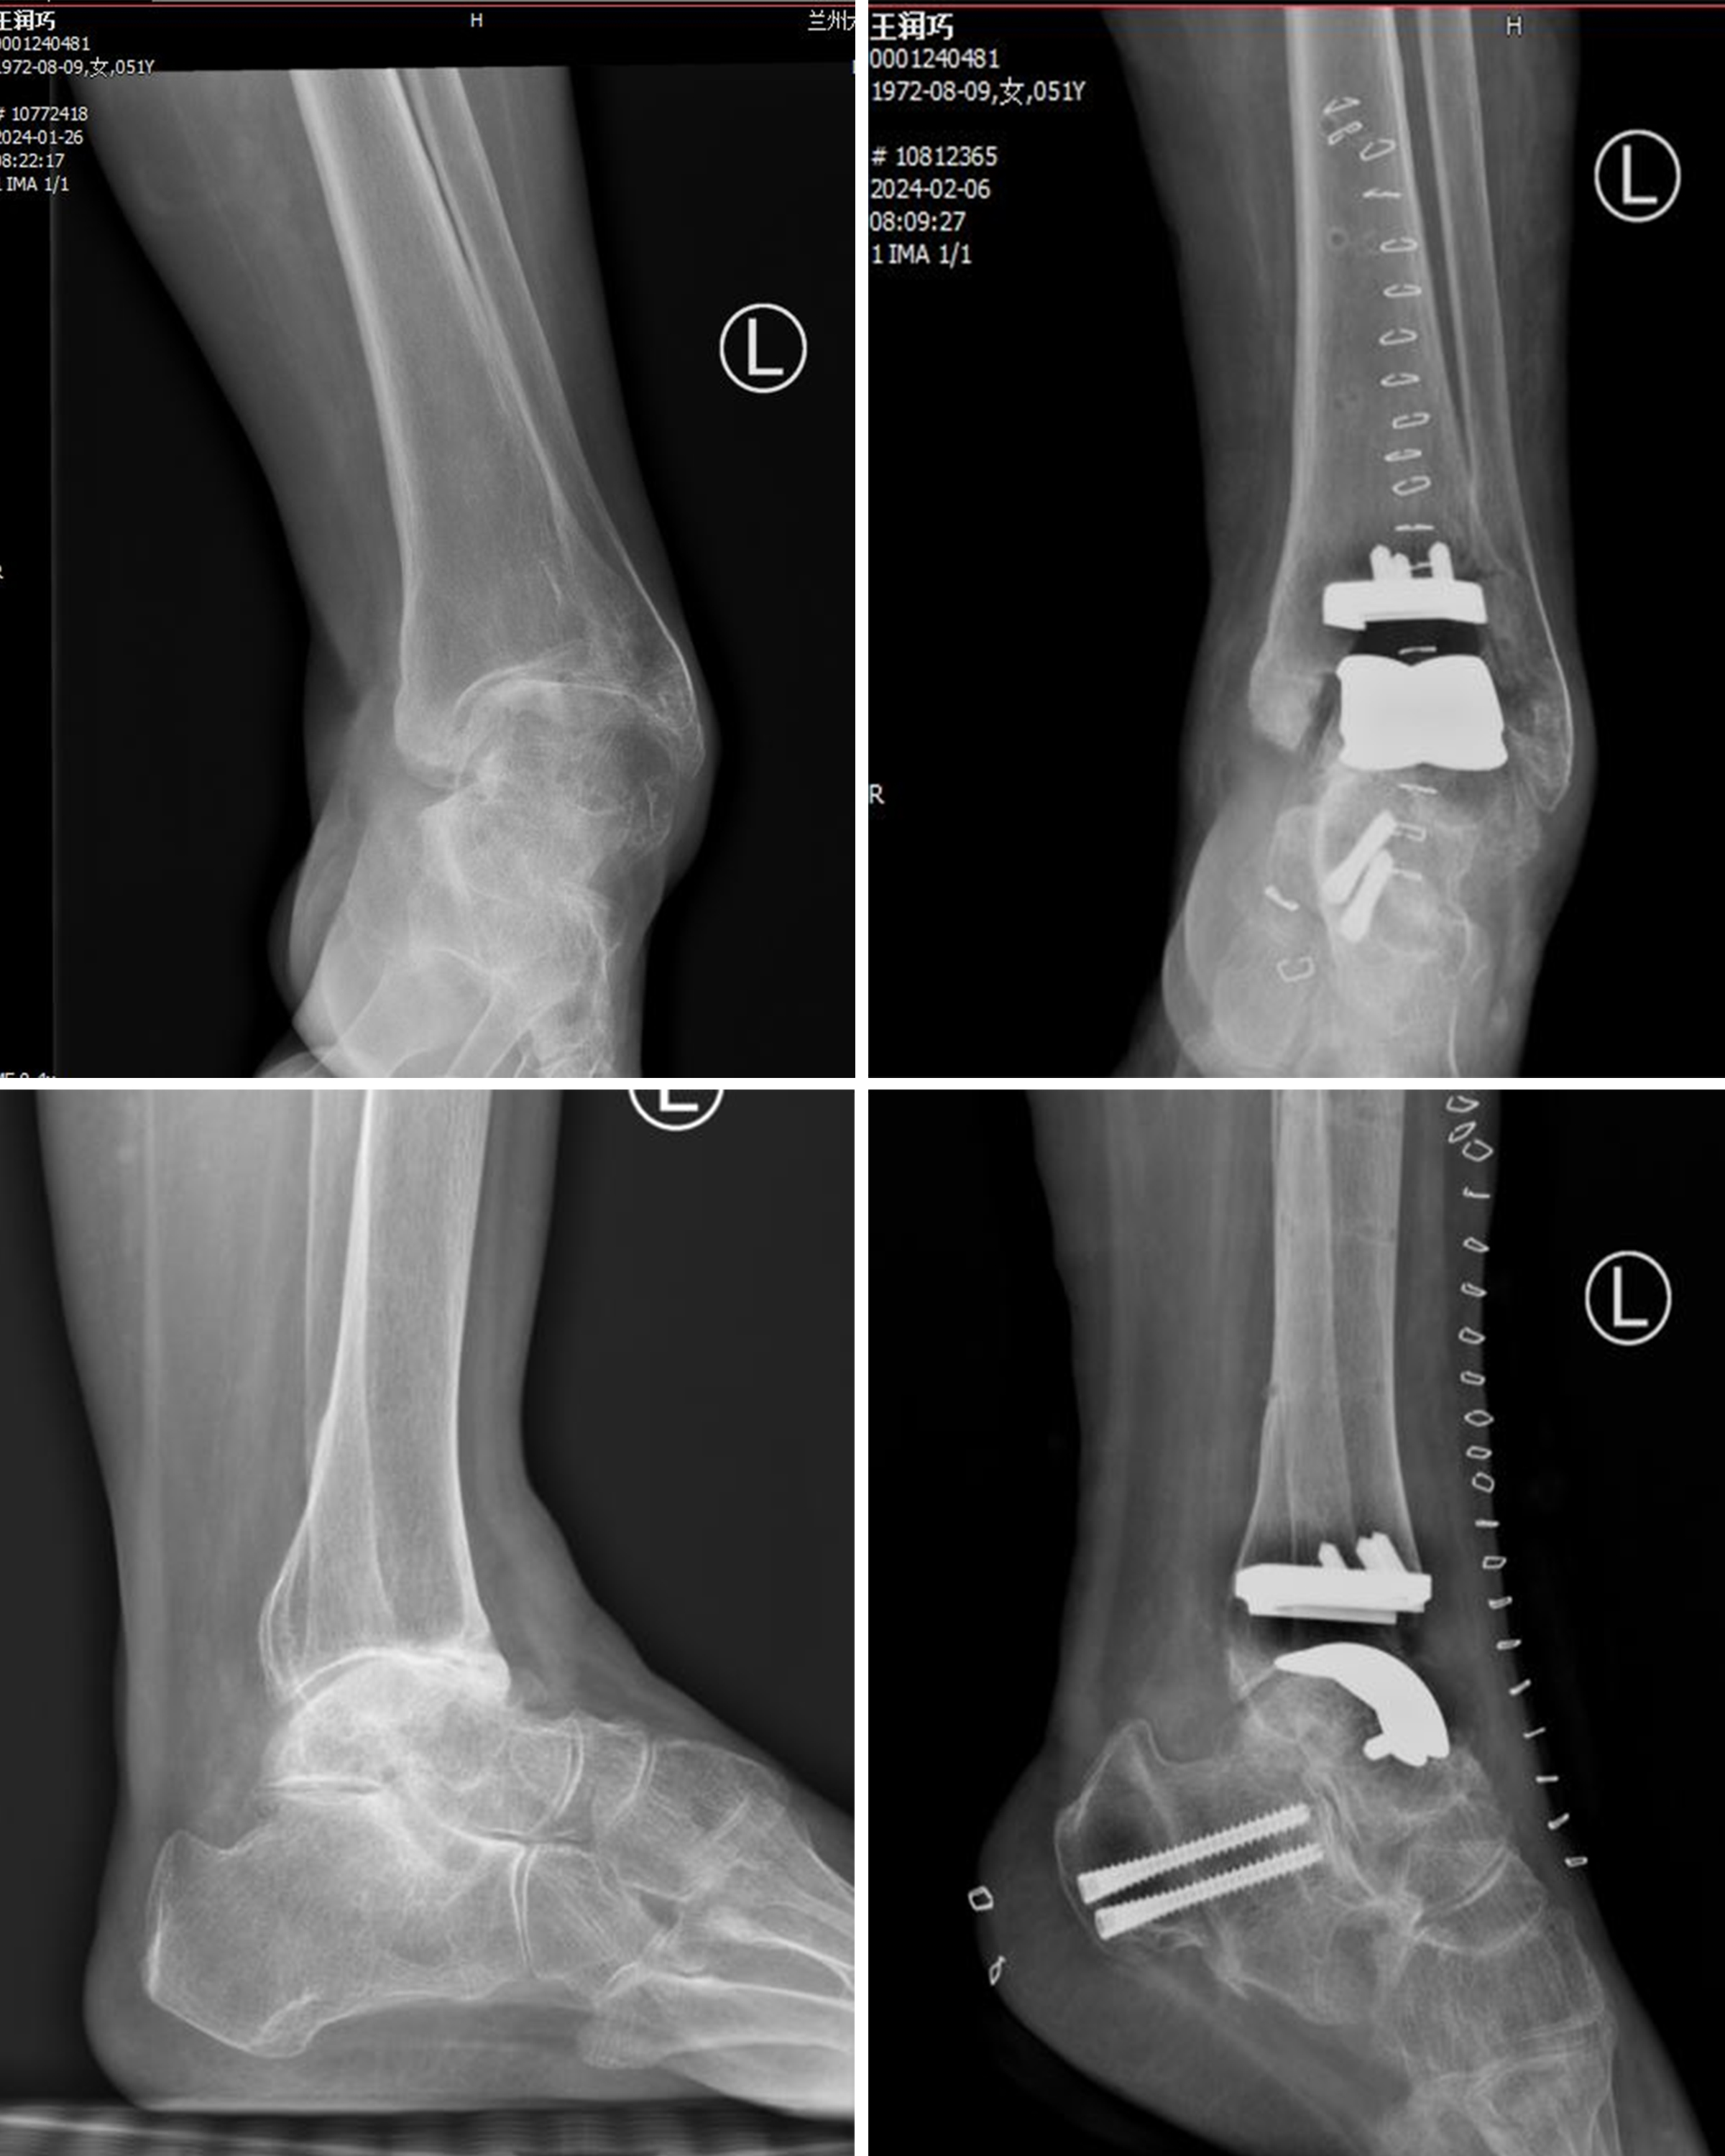

近日,兰大二院骨科四病区王凯医师团队在刘京升主任指导下完成甘肃省首例全踝关节Infinity假体置换手术,解决了一名踝关节病患者40多年的病痛。

患者为51岁女性,因踝关节疼痛40年余,由于当地医疗条件有限,一直依靠吃止痛药或物理治疗来缓解疼痛,严重影响正常生活。期间反复就诊于各大医院,因考虑踝关节融合手术后的并发症和后遗症较多,始终犹豫不决。偶然得知兰大二院有治疗踝关节病的专科,抱着试试看的心态,找到了足踝外科王凯医生。根据患者病情,经过完善的术前准备,王凯医生为患者实施了全踝关节Infinity假体置换手术,该项手术的优势在于胫关节截骨量少,可尽量保留患者的骨质,对原本的骨质破坏少,假体寿命更长,功能更好,且能促使患者更快康复。经过手术治疗,患者功能恢复良好,目前已康复出院。